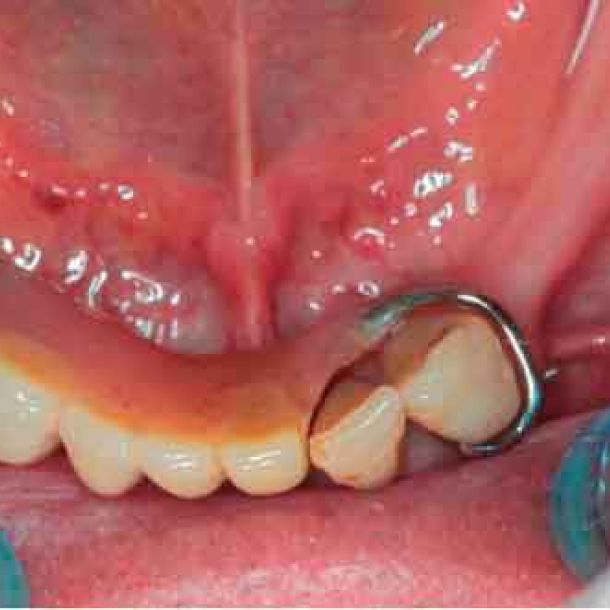

When traditional IOS scans lack necessary references, Cone Beam Computed Tomography (CBCT) data serves as a possible alternative. By utilizing CBCT scans, clinicians can establish accurate reference positions for treatment planning.

To be able to use CBCT data as initial models, we need to transform the DICOM file into an STL file.

Before acquiring the CBCT, I added 2 pieces of composite to the mandible to be able to do the picking process during jaw motion recording. This is a useful trick to remember in a situation of lacking teeth.